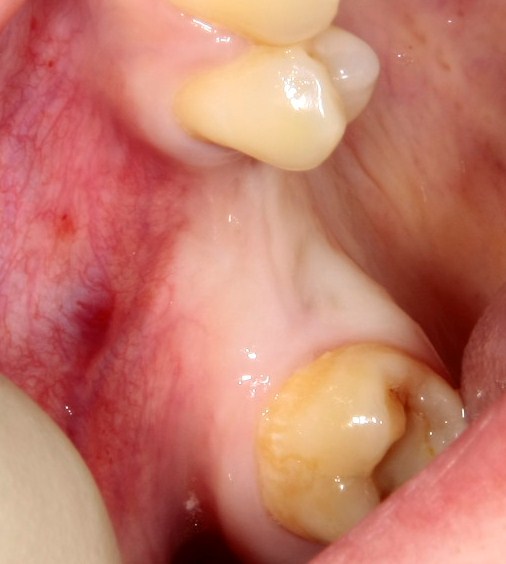

Но, если мы говорим не о поиске истины, а о выборе метода лечения? К примеру, мы столкнулись с распространенной ситуацией:

или вот:

когда атрофия альвеолярного гребня препятствует установке правильных имплантатов в правильное положение (см. Рекомендации по установке имплантов. Часть V).

Теперь возьмём клинический случай (нижняя челюсть, отсутствия 35, 36, 37 зубов, атрофия альвеолярного гребня по ширине):